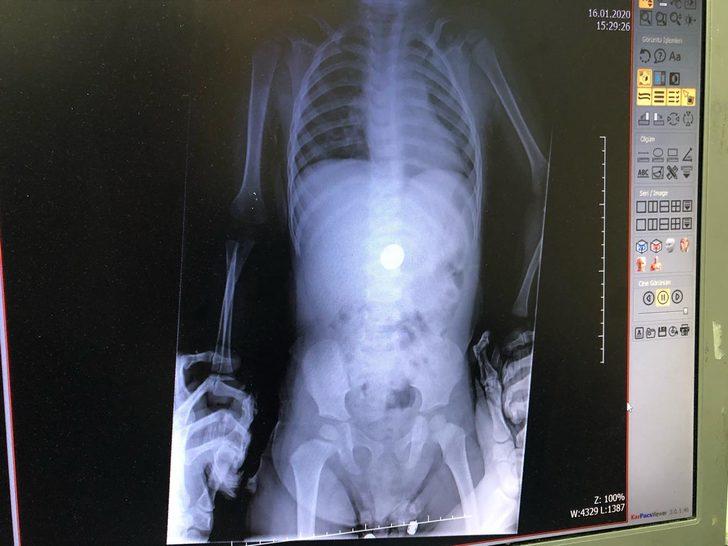

Zonguldak Kadın Doğum Çocuk Hastalıkları Hastanesi'ne 16 Ocak'ta başvuran aile, doktorlara çocuklarının madeni para yuttuğunu söyledi. Dr. Sertaç Akman, çekilen röntgende E.İ. isimli erkek çocuğun midesindeki 25 kuruşluk madeni parayı tespit etti. E.İ.'nin yapılan muayenesinde madeni paranın yemek borusuna zarar vermediği anlaşıldı. Doktorlar, gerekli tetkikleri yaptıktan sonra E.İ.'nin parayı doğal yollarla çıkarması için taburcu edip evine gönderdi. Takibe alınan E.İ.'nin normal yolla parayı çıkaramaması halinde endoskopi veya ameliyat gibi farklı yöntemlerle paranın çıkarılabileceği öğrenildi.